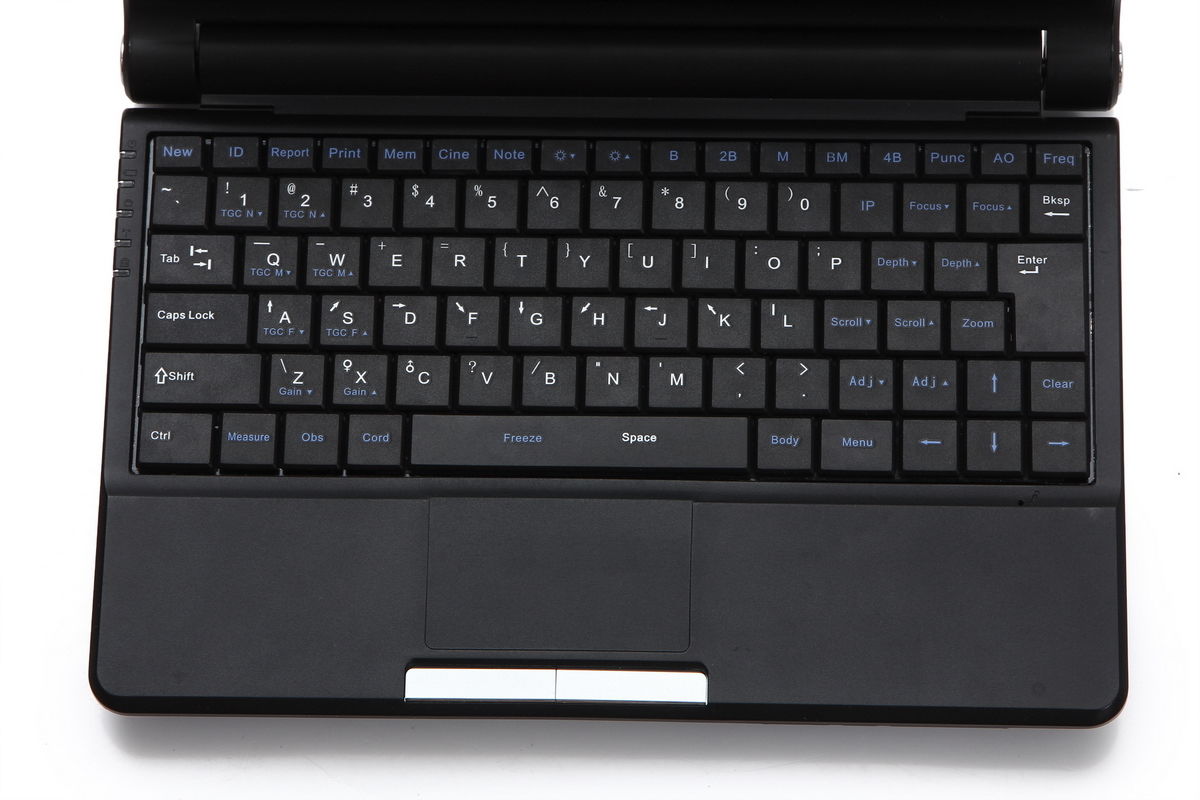

Portability and Ease of Use

One of the standout features of this ultrasound machine is its portability. Being a laptop model, it can be easily transported between different locations. However, its lightweight design does not compromise on performance. Users can quickly set it up and start conducting examinations with minimal training. This makes it a perfect tool for clinics, hospitals, and fieldwork.